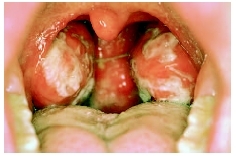

Mononucleosis = داء كثرة وحيدات النوى